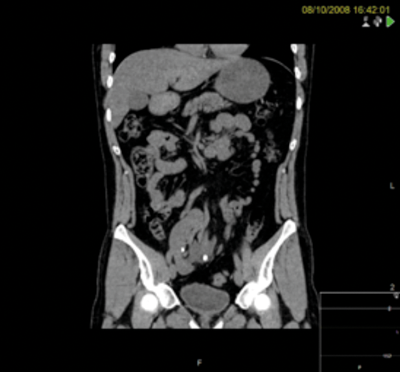

A 37-year-old male presented with stones in a right pelvic kidney. Flexible ureteroscopy demonstrated a tight and very tortuous ureter with no access to the renal pelvis.

PCNL was discussed at a specialist x-ray meeting but considered unsafe due to the risk of perforating overlying bowel.

A right sided transperitoneal laparoscopic approach was utilised, sweeping ascending colon medially. The renal pelvis was incised and stones were removed using a flexible cystoscope and the renal pelvis was closed over a stent.

At three years postoperatively, the patient was asymptomatic with stable renographic function and stone-free.

Figures above demonstrate worsening hydronephrosis preoperatively.